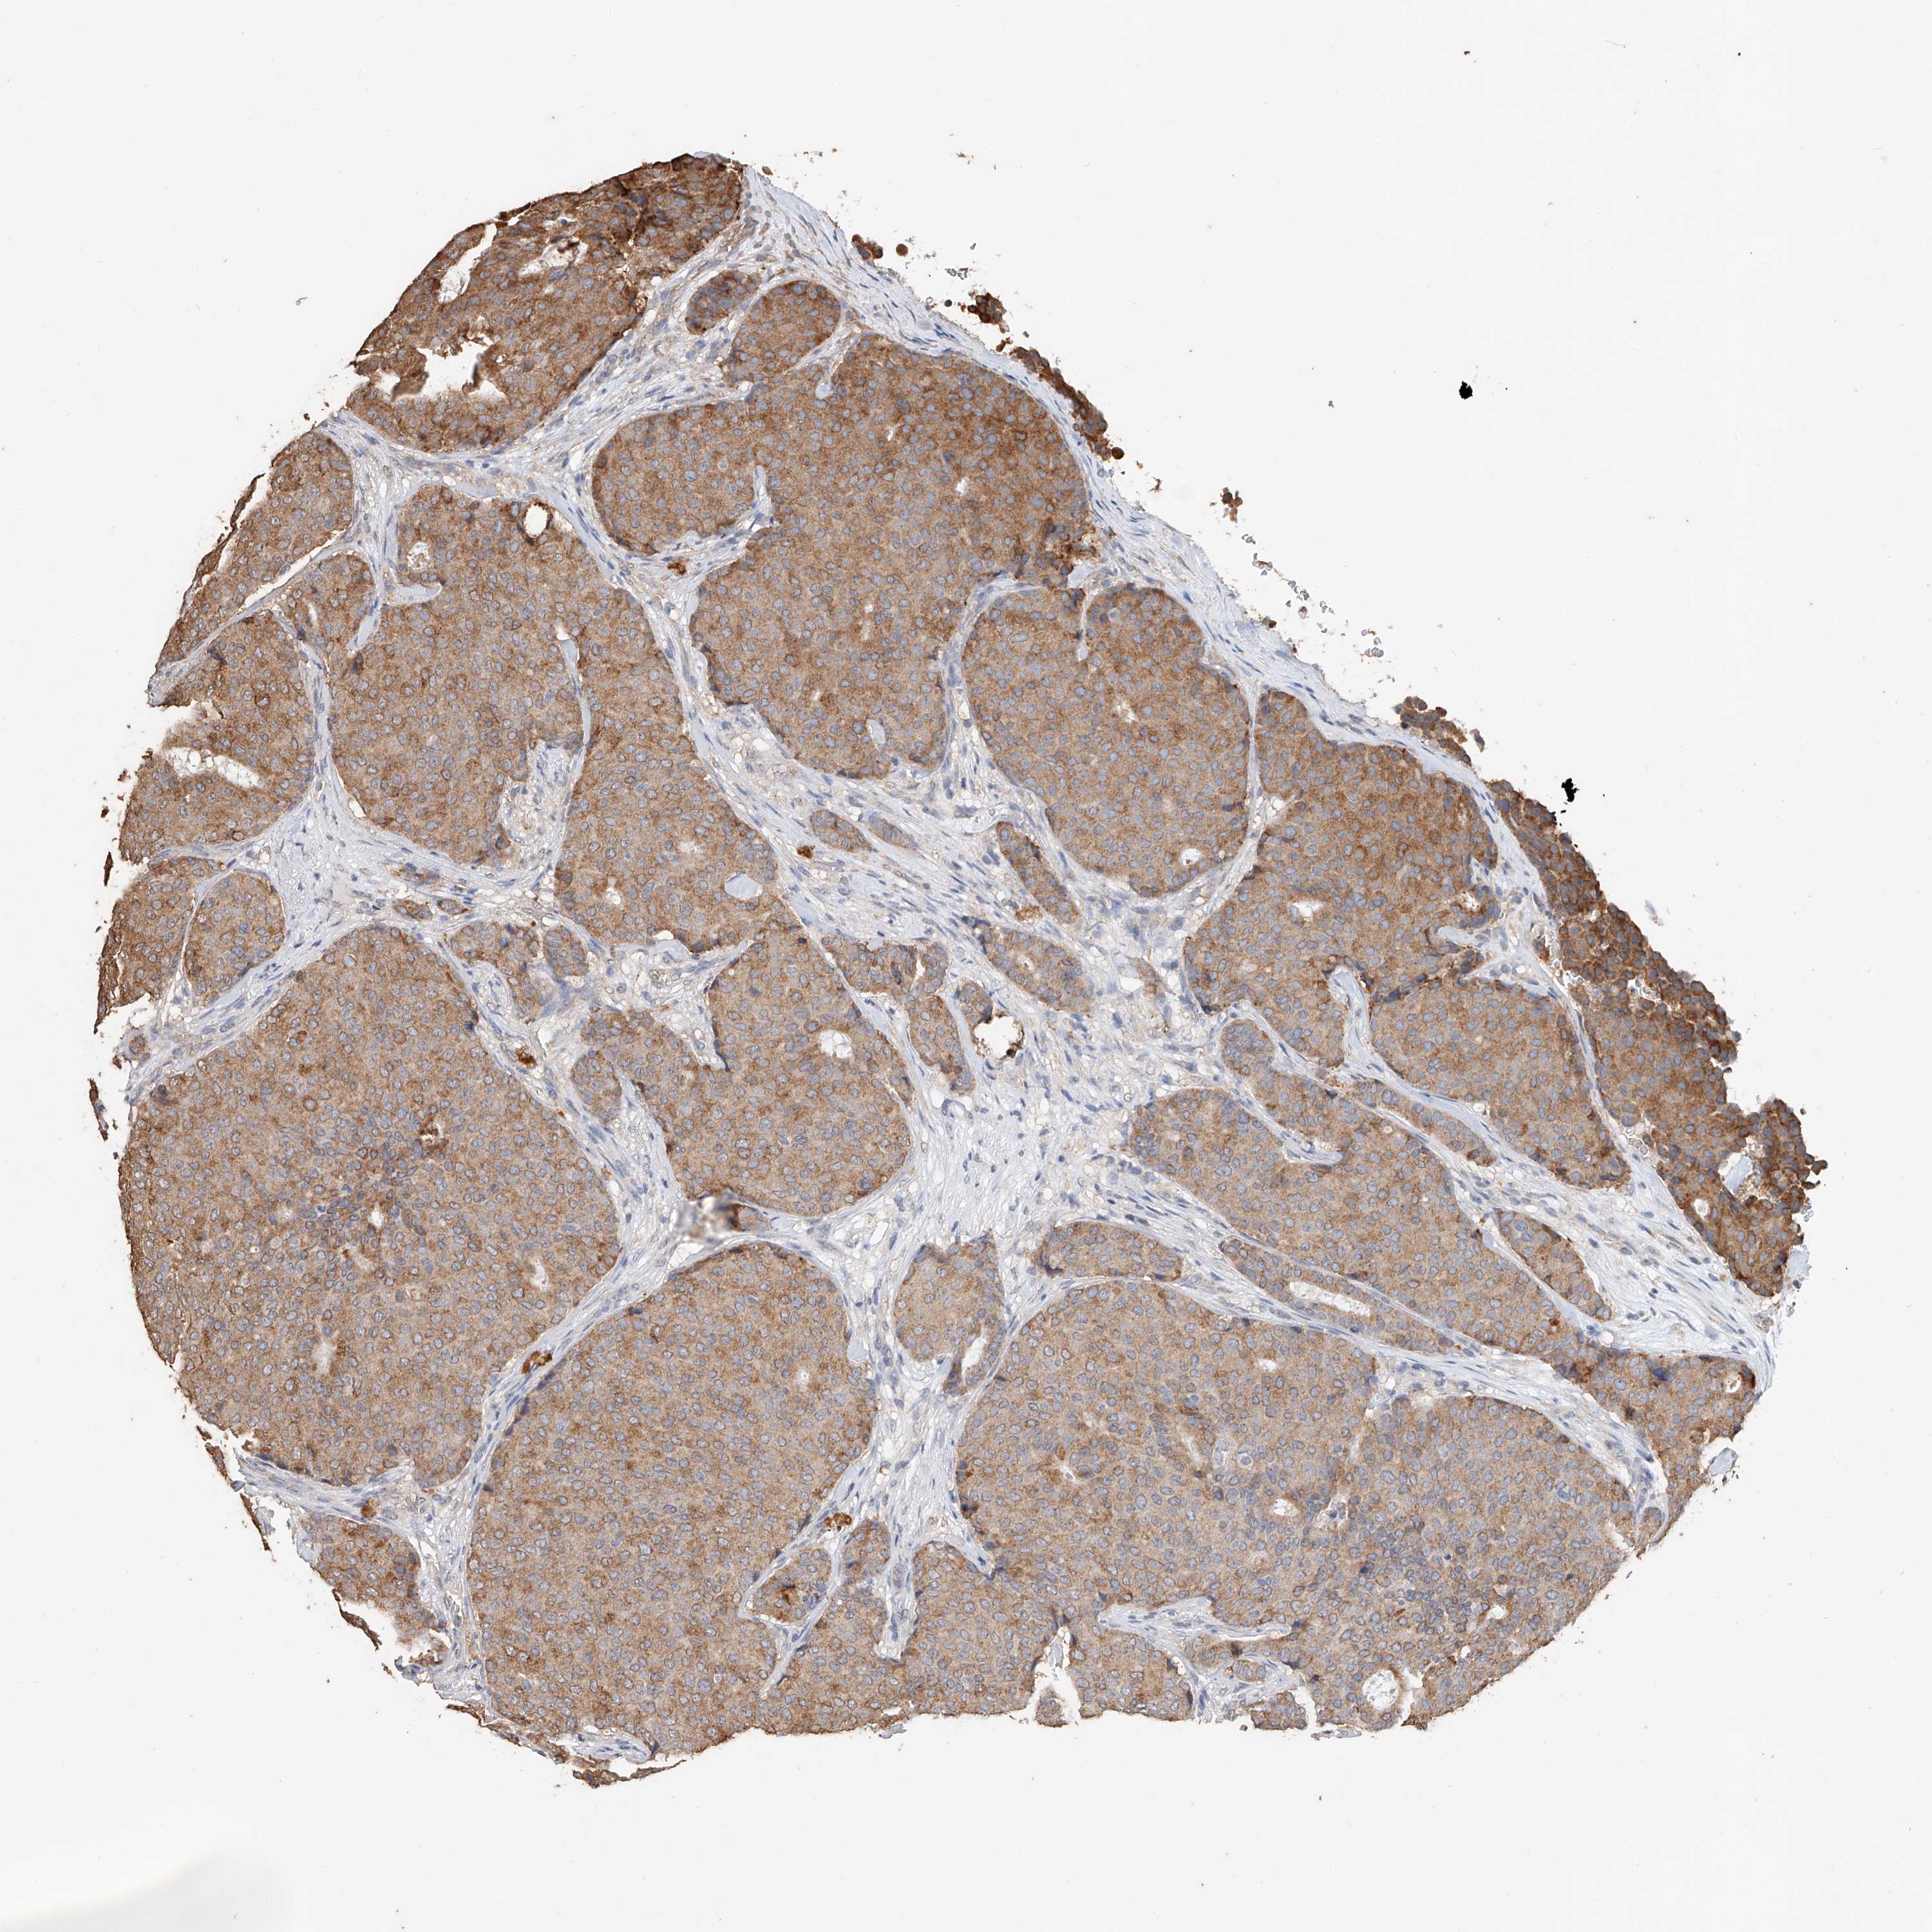

CANCER BREAST CANCER Show tissue menu

BRCA TCGA BRCA VALIDATION PROTEIN EXPRESSION